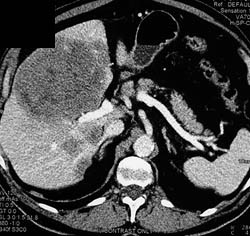

Liver Metastases